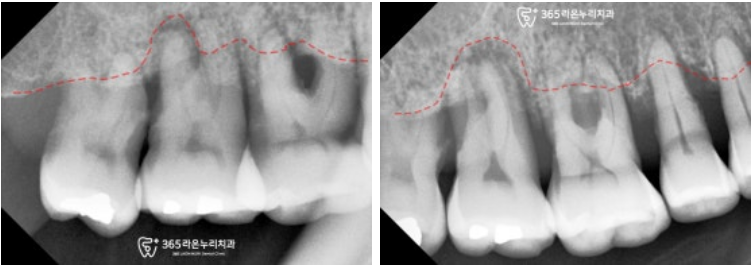

■ 2. 엑스레이 진단

남촌동 치과 에서는

전반적인 상황을 알기 위하여

파노라마 엑스레이를 찍어보았는데요,

보이는 것처럼 이가 없는 곳은

텅 비어있는 게 보이고

치조골의 높이도 낮아진 부위가 있습니다.

파노라마보다 조금 더 가까이서

높은 해상도로 볼 수 있는

치근단 사진을 찍어보니

오른쪽 위 내려간 잇몸뼈의 높이가

더욱 확실히 보이네요.

비어있는 오른쪽 아래 구치부도

마찬가지로 살펴보았는데요,

맨 뒤에 임플란트를 심어둔 곳에

염증이 생겨 주변으로 뼈가 녹아있습니다.

왼쪽 위아래도

전반적으로 뿌리 끝 염증이 심하시고

뼈가 많이 내려가신 상태로 판단됩니다.

이렇게 치아를 잡아주는

치주조직이 좋지 못하니

당연히 이가 흔들리고

저작하기에 힘든 부분이 있으셨겠네요.